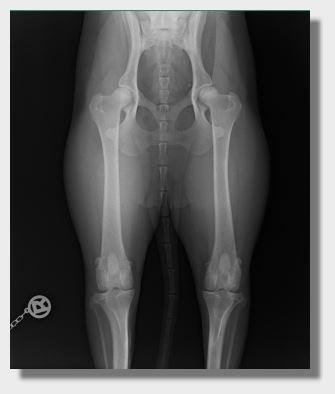

Hüftgelenksdysplasie (HD)

Eine Fehlentwicklung des Hüftgelenks nennt man Hüftdysplasie oder Hüftgelenksdysplasie. Sie kommt bei allen Hunderassen (auch bei Katzen) vor, wobei das Krankheitsbild bei großwüchsigen Rassen häufiger auftritt.

Die Fehlentwicklung kann sich auf den Oberschenkelkopf oder die Hüftgelenkspfanne beziehen. Ebenso spielt es eine Rolle, wie fest der Oberschenkelkopf in der Pfanne gehalten wird. Für die Feststellung der HD, wird unteranderem auch der Norberg-Winkel verwendet. Er sagt aus, wie weit der Oberschenkelkopf von der Hüfgelenkspfanne umschlossen wird.

Es ist auch wichtig zu wissen, dass die HD zu einem Großteil vererbbar ist, jedoch auch Fütterung und Haltung im ersten Lebensjahr eine sehr große Rolle spielen.

Außerdem muss noch gesagt werden, dass Hunde die mit einer C-Hüfte ausgewertet wurden wahrscheinlich in ihrem ganzen Leben (auch als Vollgebrauchshunde) keine Probleme haben werden. Sie dürfen nur, im Gegensatz zu anderen Länderen, in Deutschland nicht mehr zur Zucht eingesetzt werden. Heute wird nur noch mit A oder B Hüften gezogen. Bis vor einigen Jahren war das, auch hier in Deutschland, noch möglich.

Trotz aller Bemühungen die HD immer mehr auszumerzen, tritt sie doch gelegentlich bei dem Versuch frisches Blut in die Zucht zu bringen, etwas was unbedingt von Nöten ist um den geringen Genpol in Deutschland nicht noch mehr zu verkleinern, auf.